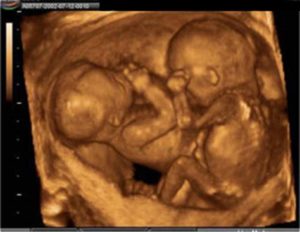

Каждый ваш малыш на этой неделе весит почти 500 гр и имеет длину 28-29см. Из-за периода интенсивного роста вашей двойни в ближайшие недели вы можете испытывать довольно сильный дискомфорт.

Малыши на этом сроке уже активно двигаются и вы должны ощущать их движения каждый день. Большинство беременных двойней на 23 неделе еще не могут точно определить, какой из малышей двигается в данный момент. Это нормально.

Живот будущей матери уже ощутимо поднялся над лобком, и она может испытывать трудности с дыханием. Малыши достигли длины примерно в 27 см и веса в 400 грамм.

УЗИ на этом сроке может показать разницу в весе и росте близнецов, однако это не является поводом для беспокойства.